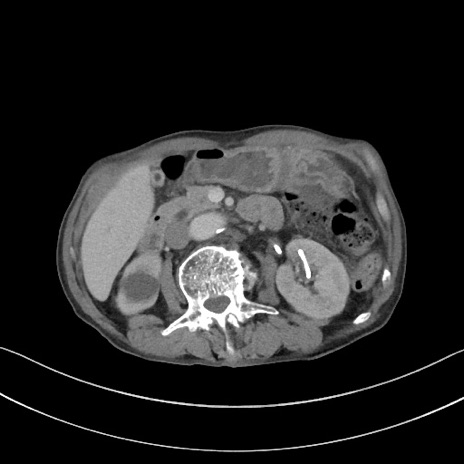

症例3(横断像)

【症例】 70歳代男性

【主訴】右鼠径部腫瘤、疼痛

【現病歴】本日朝より上記主訴あり、受診。

【既往歴】膀胱癌にて膀胱全摘、両側尿管皮膚瘻

【データ】WBC 5600、CRP 0.56